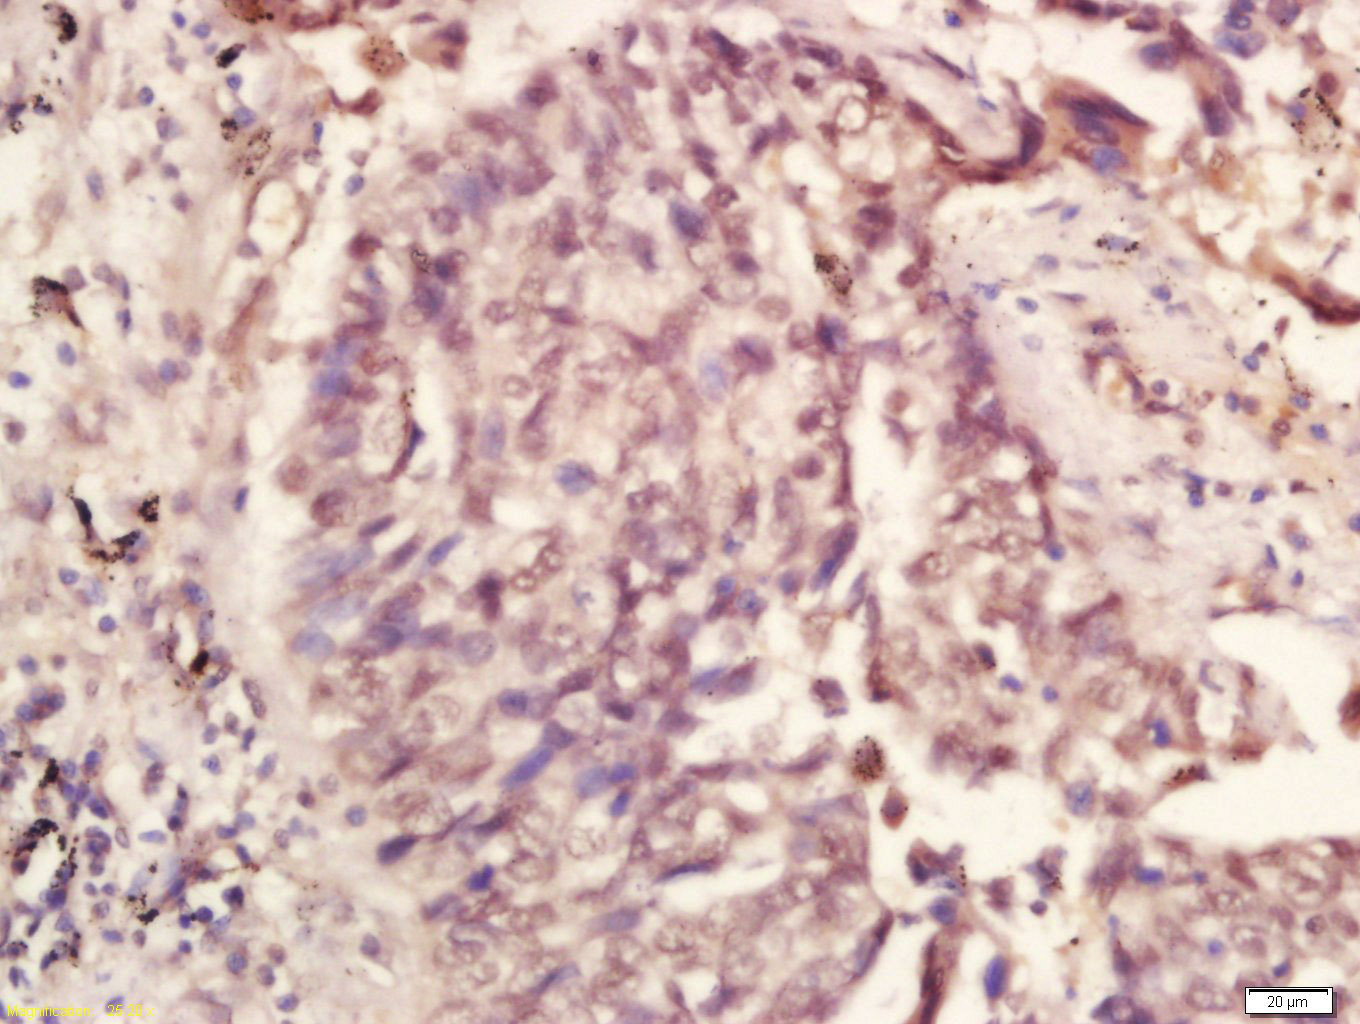

Paraformaldehyde-fixed, paraffin embedded (rat brain); Antigen retrieval by boiling in sodium citrate buffer (pH6.0) for 15min; Block endogenous peroxidase by 3% hydrogen peroxide for 20 minutes; Blocking buffer (normal goat serum) at 37°C for 30min; Anti

Tissue/cell: human lung carcinoma; 4% Paraformaldehyde-fixed and paraffin-embedded; Antigen retrieval: citrate buffer ( 0.01M, pH 6.0 ), Boiling bathing for 15min; Block endogenous peroxidase by 3% Hydrogen peroxide for 30min; Blocking buffer (normal goa

Paraformaldehyde-fixed, paraffin embedded (rat heart); Antigen retrieval by boiling in sodium citrate buffer (pH6.0) for 15min; Block endogenous peroxidase by 3% hydrogen peroxide for 20 minutes; Blocking buffer (normal goat serum) at 37°C for 30min; Anti

Paraformaldehyde-fixed, paraffin embedded (rat lung); Antigen retrieval by boiling in sodium citrate buffer (pH6.0) for 15min; Block endogenous peroxidase by 3% hydrogen peroxide for 20 minutes; Blocking buffer (normal goat serum) at 37°C for 30min; Antib